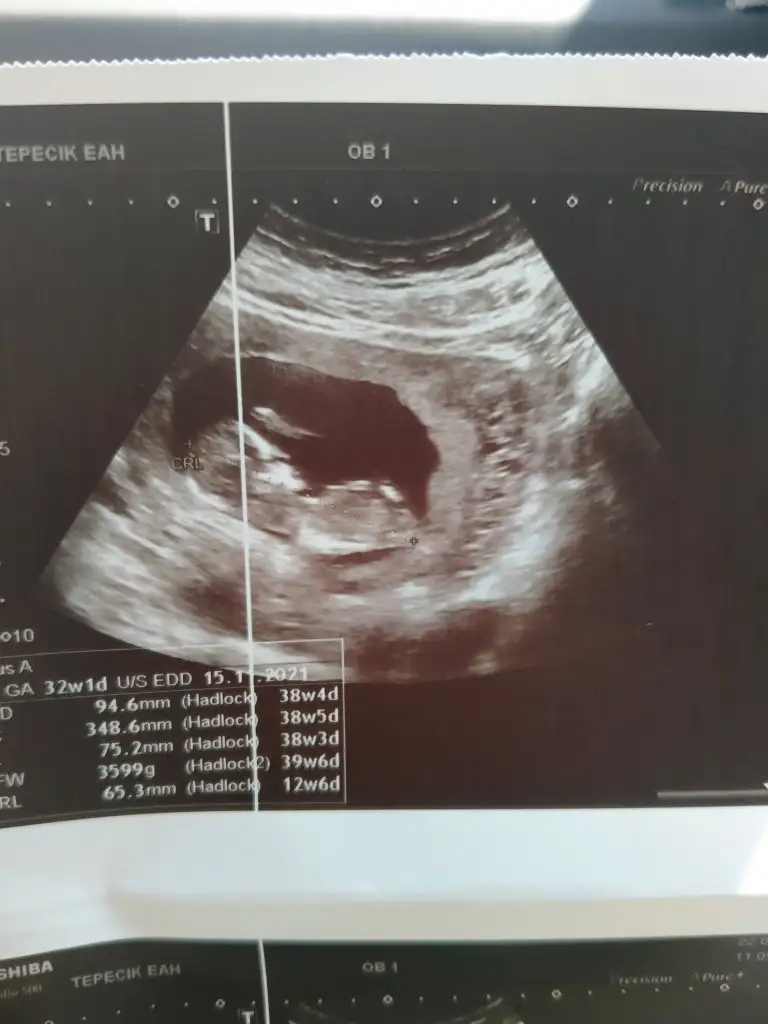

Kuzum tahmin edebilecek misin 12+5 en net resmi 🤷

IMG20210922120304.webp

26,2 KB · Görüntüleme: 116

Kızlar bı arkadaş keseye göre tahmin yapıyor ve hep tutuyormuş iki oğlunu da bu şekilde cok yeniyken bile tahmin etmiş...ogullarinda kesesi hep uzunmuş muz gibi...yuvarlak ve yuvarlağa yakın olanlar hep kızdır diyor..ve bayağı emin konusuyor..benimki şişman bı fasulye gibi oo kesin kız görürsün dedi...sizlerin keselerinin şekli nasıldı ve cinsiyet neydi konusalimmi 😊